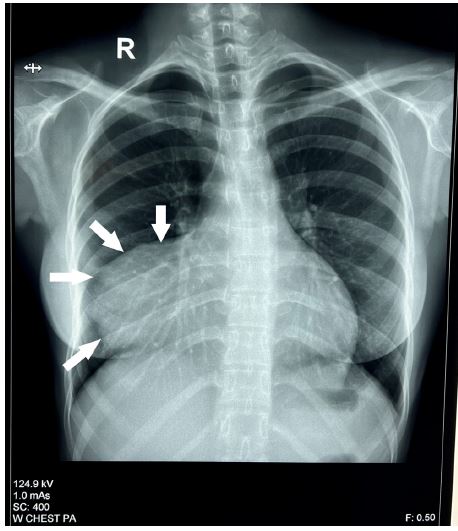

A 17-year-old female presented with symptoms of palpitations and dyspnea on exertion (New York Heart Association class III) for three months duration. The electrocardiogram showed sinus tachycardia. Chest X-ray revealed marked cardiomegaly (cardiothoracic ratio 0.7), and a large outpouching of the RA (Figure 1). Two-dimensional transthoracic echocardiography (TTE) showed a diverticulum (10 x 8 x 6 cm), communicating with the free wall of RA. The tricuspid valve was normal. The patient was offered the surgical option of resection of the diverticulum, and her family consented to the same.

Figure 1: Chest X-ray showing cardiomegaly and outpouching of the right atrium (arrows).